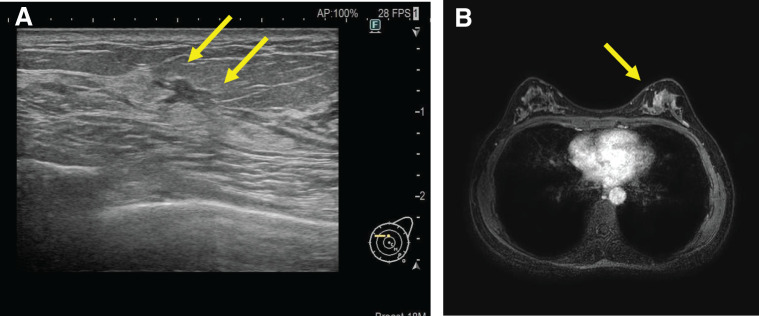

Case presentation: We performed R-NSM for a 41-year-old Japanese woman with cTisN0M0 breast cancer. NSM and IBR to place a tissue expander (TE) into the post-pectoral pocket were performed using the da Vinci SP surgical system with the double bipolar method.